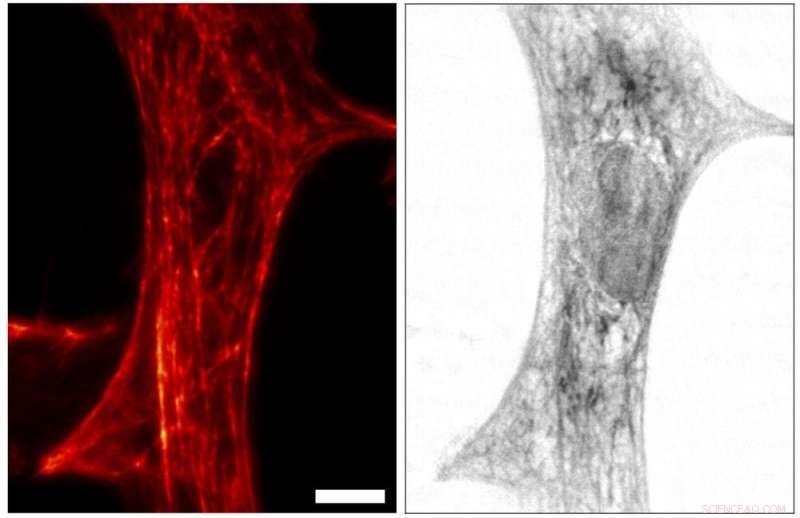

STED image (left) and X-ray imaging (right) of the same cardiac tissue cell from a rat. For STED, the network of actin filaments in the cell, which is important for the cell’s mechanical properties, have been labeled with a fluorescent dye. Contrast in the X-ray image, on the other hand, is directly related to the total electron density, with contributions of labeled and unlabeled molecules. By having both contrasts at hand, the structure of the cell can be imaged in a more complete manner, with the two imaging modalities “informing each other”. Credit: University of Göttingen, M. Bernhardt et al.

"With this novel X-ray/STED microscope we have visualised a network of protein filaments in heart muscle cells in STED mode first. The cells were then also imaged by X-ray holography to cover the spatial distribution of mass density in the entire cell, including all of its components," explains Marten Bernhardt, lead author of the article. "By using complementary contrast we aim at a more complete understanding of the structure underlying contractibility and force generation in the cells," adds Salditt. "In future, we want to apply this also to observe dynamic processes in living cells," explains Köster, spokesperson of the collaborative research centre Collective behaviour of soft and biologcal matter of the German Science Foundation (DFG), which provides the research framework of the experiments.